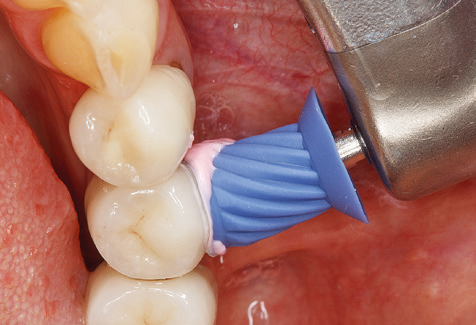

Fig. 9: The accessible implant and tooth surfaces are polished with polishing cups and suitable polishing compounds. – Fig. 10: Repeat instruction in the use of appropriate aids for oral hygiene at home should also form part of SPT. – Fig. 11a and b: Clinical situation 12 years after insertion of the prosthetic restoration. During this period, only a veneering ceramic fracture on tooth 47 and the requirement for endodontic treatment of tooth 12 were observed. All restorations are still functioning as intended.

Following machine cleaning of the tooth and implant surfaces, the surfaces of the natural teeth are cleaned manually using standard hand instruments. When performing manual cleaning, particular attention must be given to maintaining the correct angle of application, appropriate sharpness, good support and working with the curette from apical to coronal. Either titanium or carbon curettes should be used for post-cleaning of the implant structures (Fig. 8). In addition to the use of ultrasonic devices, power jet devices can also be used in conservative dentistry. However, it must be taken into consideration that these procedures are not suitable for removing hard deposits and thus they cannot replace the use of hand instruments and ultrasonic instruments completely. In all cases, cleaning is followed by mechanical polishing of the accessible tooth and implant surfaces with polishing cups and polishing compounds (Fig. 9).